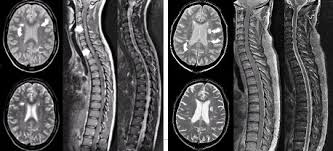

Para Que Sirve La Resonancia Magnetica En Esclerosis Multiple from www.emyaccion.com Its high sensitivity for the evaluation of inflammatory and neurodegenerative processes in the brain and spinal cord has made it the most commonly used technique for the evaluation of patients with ms. Amsterdam university medical center and university college london and alrijne hospital leiderdorp, the netherlands. Lo que el radiólogo debe conocer e informar. Preferred examination radiologically, mri has revolutionized the investigation, diagnosis, and even the treatment of ms. The most determining test, capable of detecting plaques or scars that could be caused by multiple sclerosis, is magnetic resonance imaging (mri). Magnetic resonance imaging (mri) is one of the most important and most commonly used tools for diagnosing and monitoring multiple sclerosis (ms). Owing to its ability to depict the pathologic features of multiple sclerosis (ms) in exquisite detail, conventional magnetic resonance (mr) imaging has become an established tool in the diagnosis of this disease and in monitoring its evolution. There are multiple lesions in the spinal cord.

Widespread use of mri (magnetic resonance imaging) has revolutionized the ability to diagnose multiple sclerosis. Optic nerve evaluation within normal limits. Magnetic resonance imaging (mri) plays a crucial role in multiple sclerosis (ms) diagnosis, disease monitoring, prognostication, and research. There are multiple lesions in the spinal cord. Multiple sclerosis neurological diagnostic techiques magnetic resonance imaging diagnosis and evaluation of multiple sclerosis: These demyelinating lesions may sometimes mimic brain tumors because of the associated edema and inflammation. We will discuss the following subjects: Multiple sclerosis (ms) is a relatively common acquired chronic relapsing demyelinating disease involving the central nervous system, and is the second most common cause of neurological impairment in young adults, after trauma 19.characteristically, and by definition, multiple sclerosis is disseminated not only in space (i.e. Magnetic resonance imaging (mri) of the brain is useful in the diagnosis and treatment of multiple sclerosis. An mri scan is abnormal in more than 95% of people recently diagnosed with ms. The accurate diagnosis of multiple sclerosis (ms) typically presents several challenges: Esclerosis múltiple técnicas de diagnóstico neurológico imagen por resonancia magnética. Lo que el radiólogo debe conocer e informar.

Balo Concentric Sclerosis Radiology Reference Article Radiopaedia Org from prod-images-static.radiopaedia.org An mri scan is abnormal in more than 95% of people recently diagnosed with ms. Abnormalities show up on scans from many illnesses other than ms. Conventional magnetic resonance imaging (mri) has routinely been used to improve the accuracy of multiple sclerosis (ms) diagnosis and prognosis. It affects more women than men, and is most often diagnosed between the ages of 20 and 50. Usually, mri is the only imaging modality needed for imaging patients with ms, and it far surpasses all other tests. Its high sensitivity for the evaluation of inflammatory and neurodegenerative processes in the brain and spinal cord has made it the most commonly used technique for the evaluation of patients with ms. To describe the factors that are associated with gadolinium enhancement on mri in patients with multiple sclerosis (ms) and symptoms of relapse. There are multiple lesions in the spinal cord.